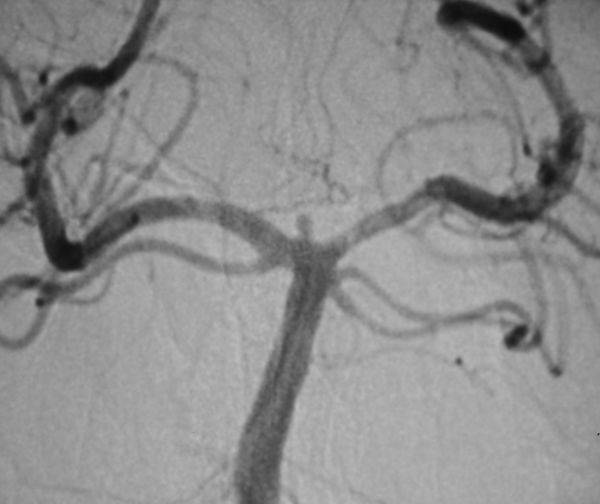

病例2、微小动脉瘤栓塞:女性,52岁,基底动脉顶端微小动脉瘤破裂出血,动脉瘤大小约1.5X1mm,位置深,周围重要结构多,手术夹闭困难,经全科医生认真分析,决定采取支架辅助+弹簧圈栓塞的方法,介入栓塞治疗,3月18日,孟祥靖主任在介入科、麻醉科的大力配合下,栓塞取得圆满成功,目前患者已痊愈出院。

病例2:基底动脉顶端微小动脉栓塞术前、后